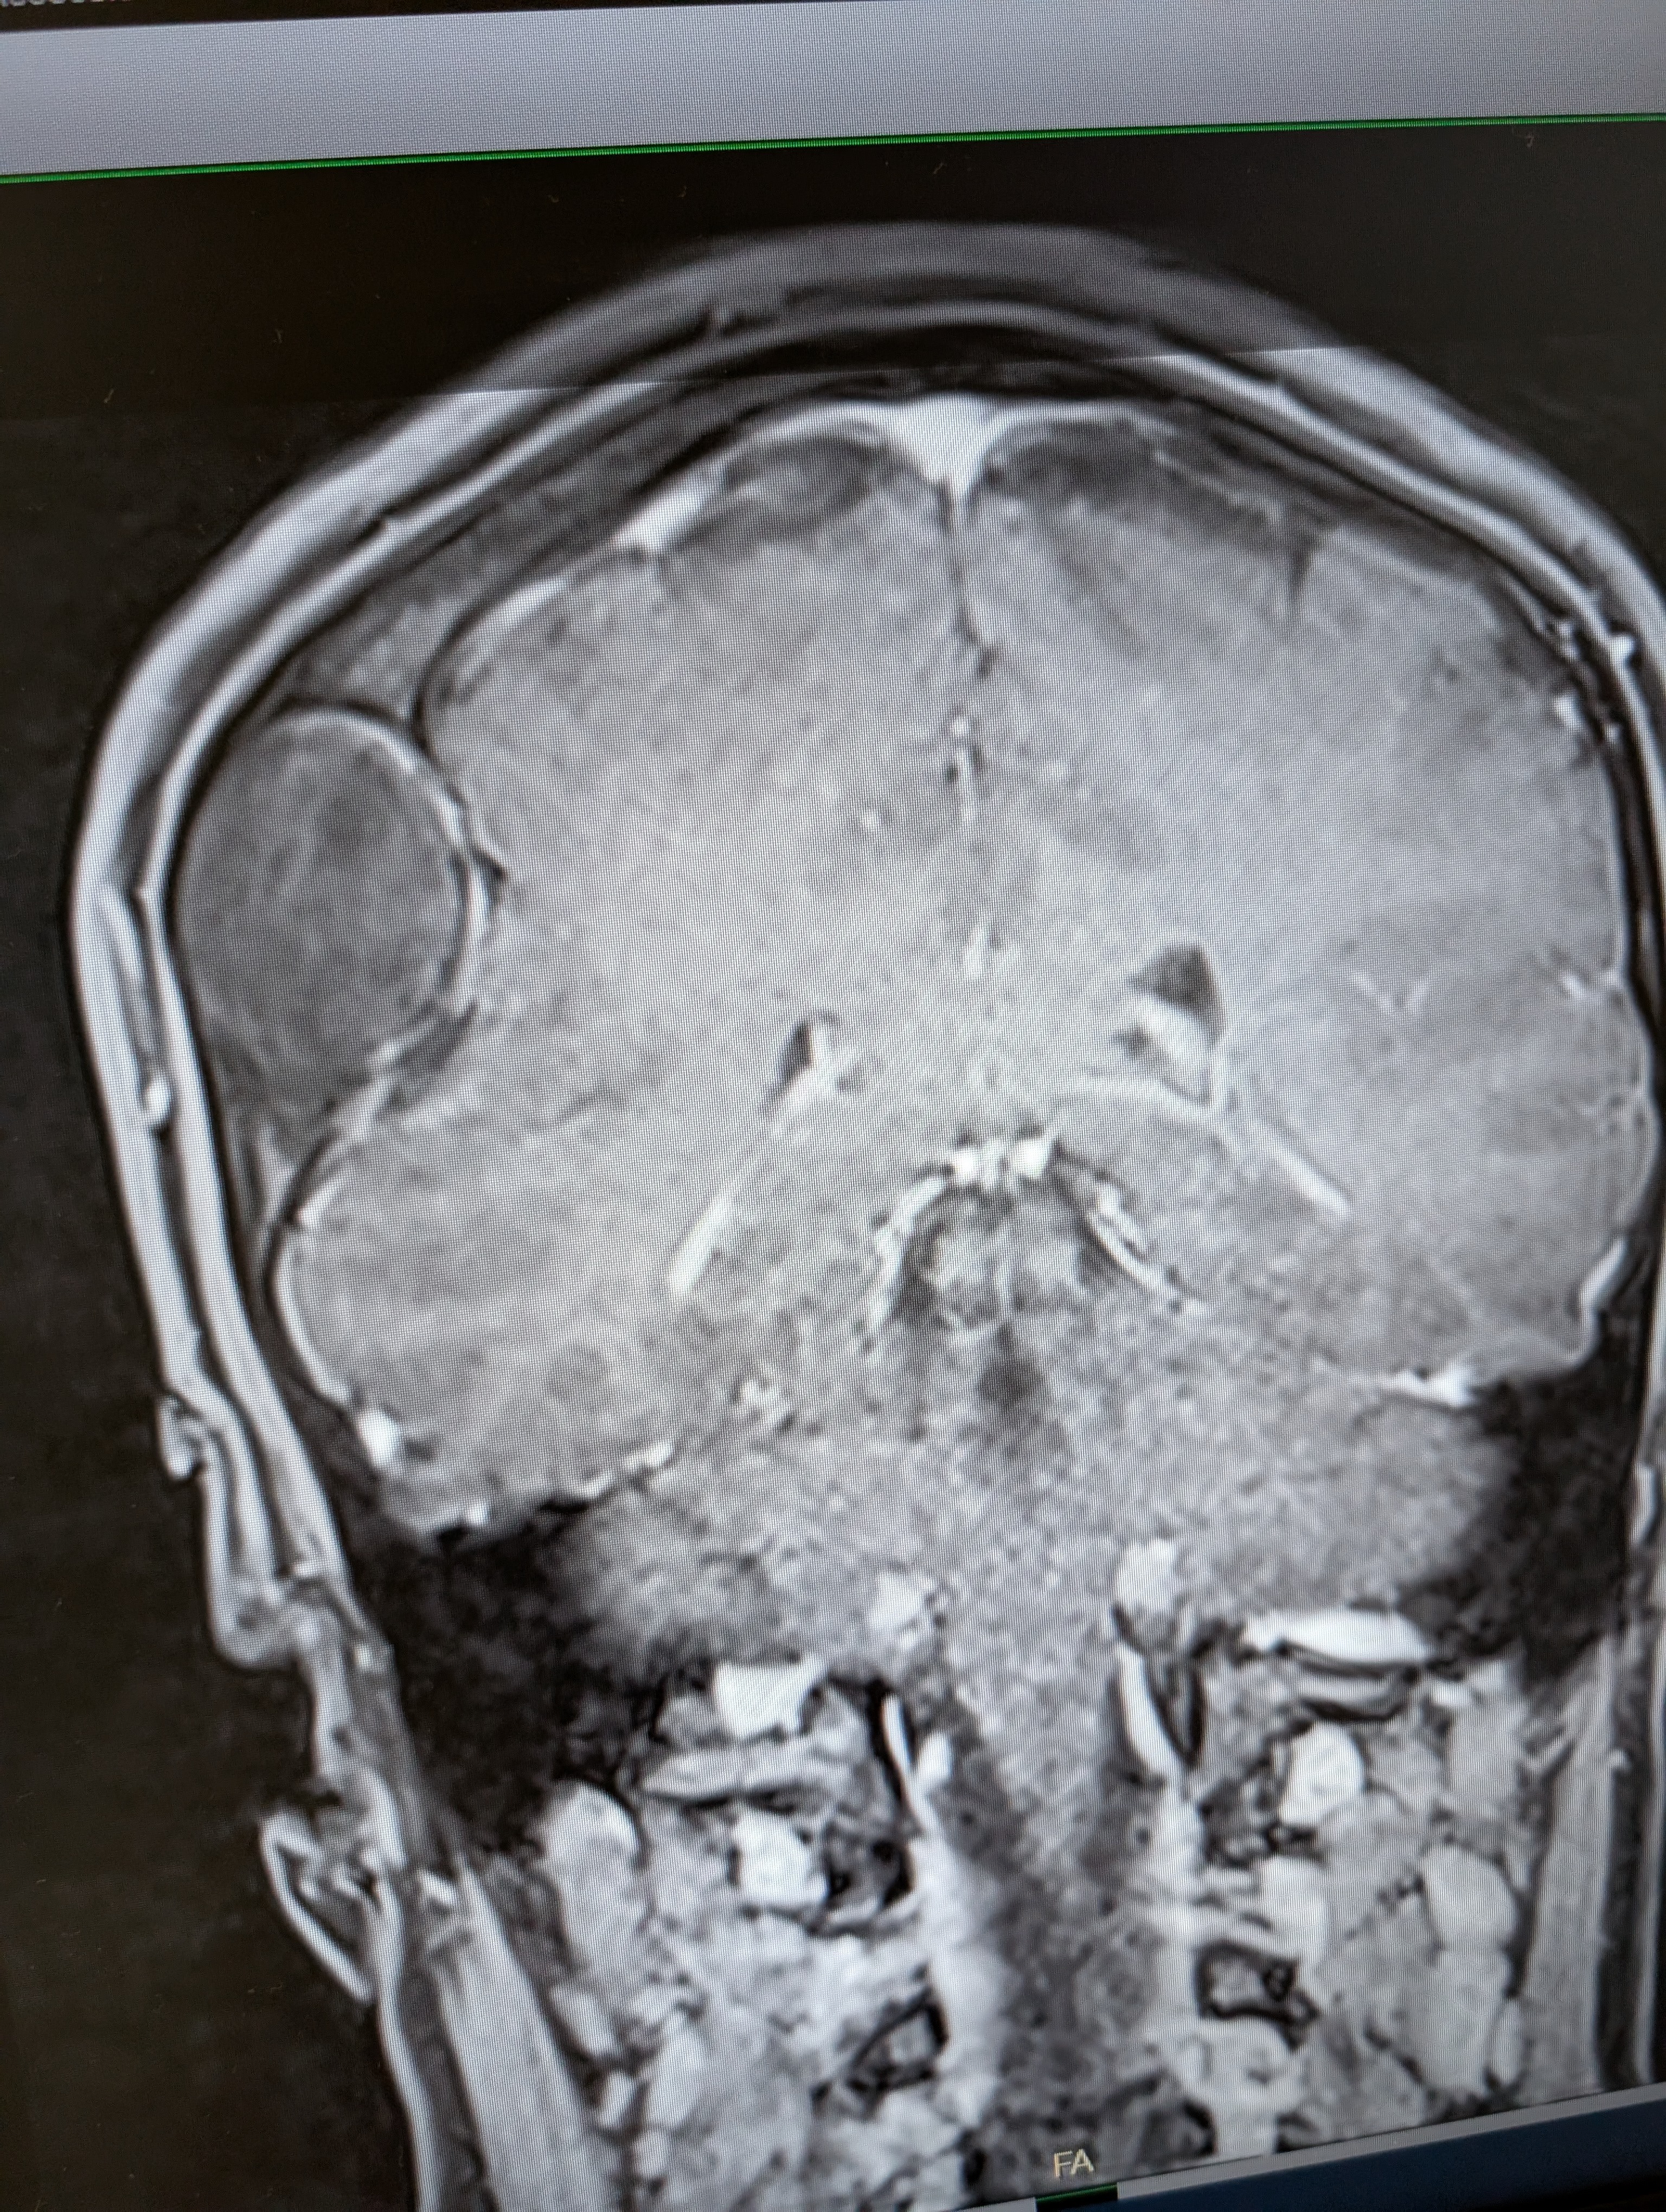

They did an MRI and two doctors came in to tell her:

Not just a call—the Vice Chair of Academic Affairs and Co-Director of the Skull Base Surgery Program at OSU personally reached out to say he had reviewed everything and confirmed:

It’s a benign bone tumor in her skull bone—something she was born with—and it CAN be removed.